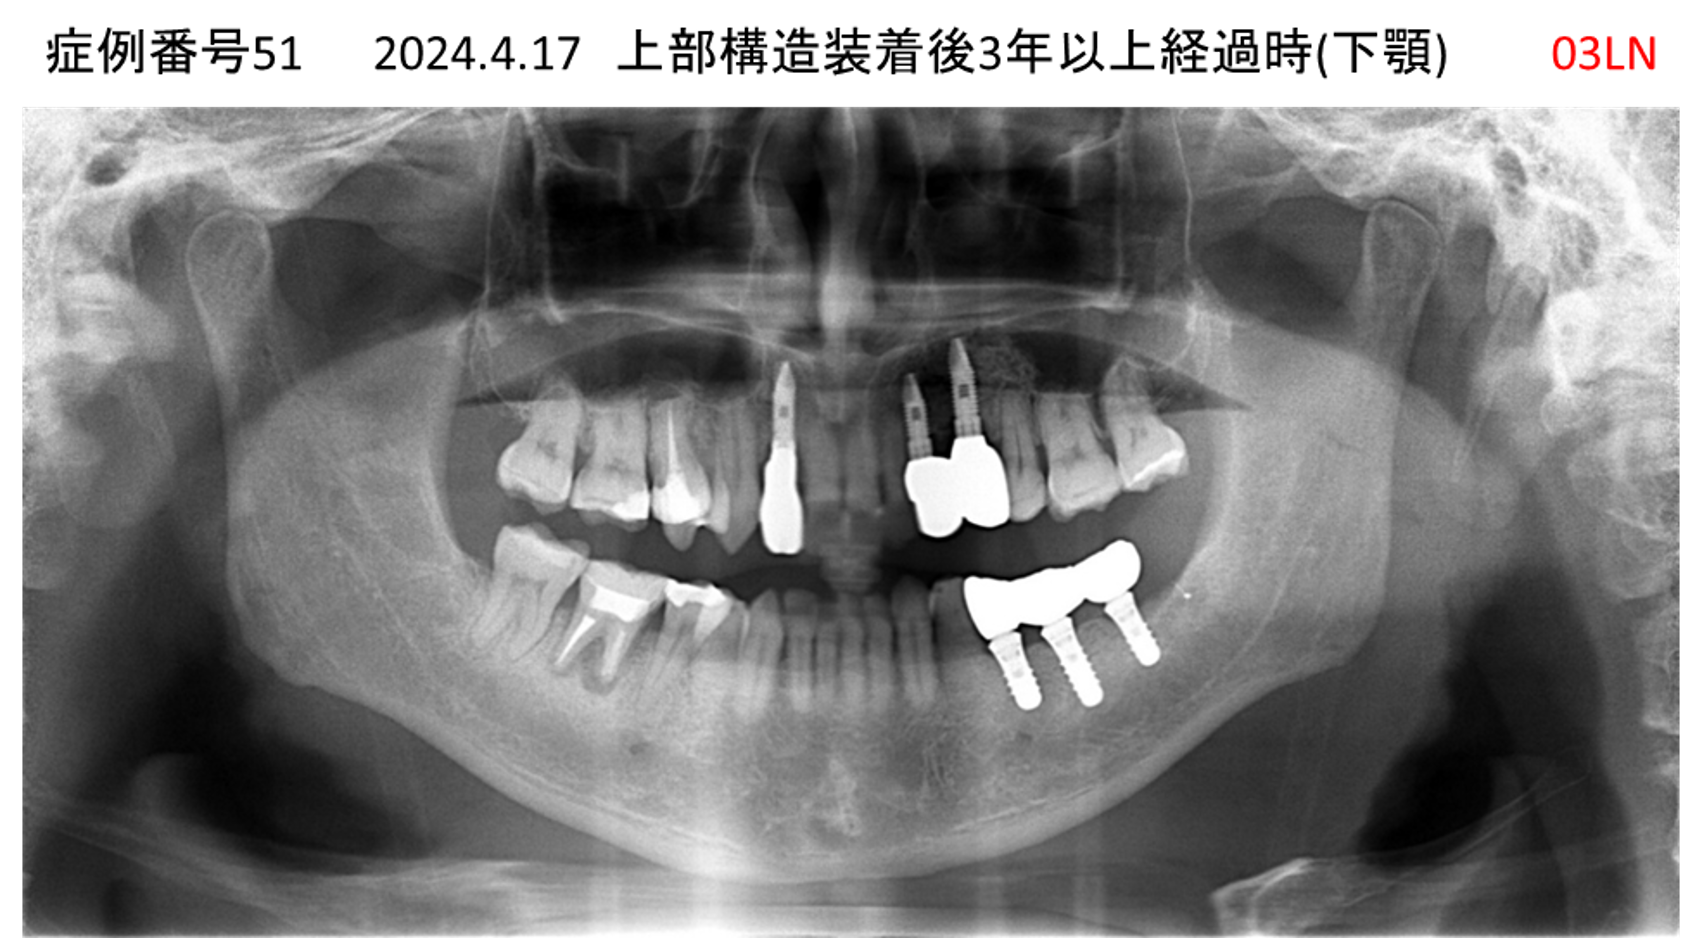

ご飯を美味しく食べたい/人前で笑えるようになりたい患者様のインプラント症例

| 治療名称 |

インプラント |

| 治療費用 |

480万円+税 |

| 治療期間 |

6か月 |

| 患者さんの症状(主訴) |

おいしいご飯が食べられるようになりたい 人前で笑えるようになりたい |

| 治療内容 |

サイナスリフト 抜歯即時インプラント |

| 治療結果 |

何でも食べられるようになった 人前で大口を開けて笑えるようになった |

| 治療の注意点(リスク/副作用) |

インプラントが壊れた場合は再治療が必要 |